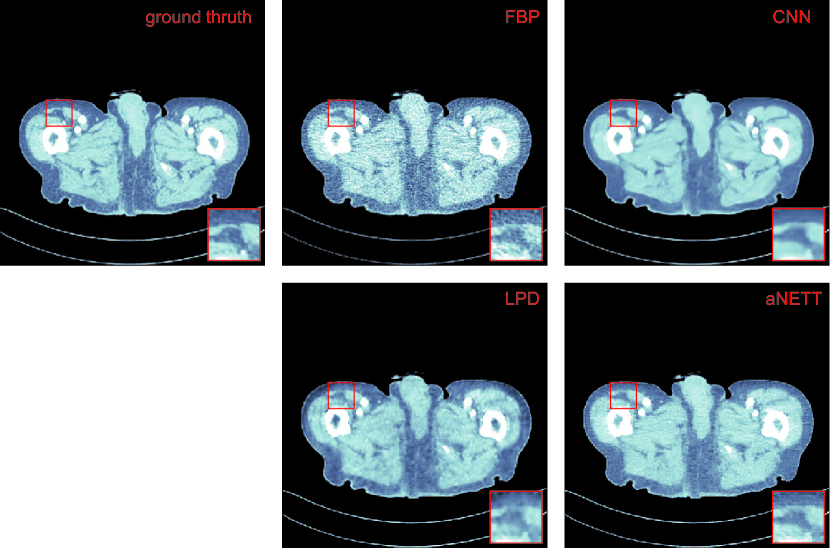

Refer to caption

Figure 4.3: Universality of aNETT due to change of angular sampling pattern. Top row: Ground truth and reconstructions from 40 angular directions. Bottom: Reconstructions from 160 angular directions. All reconstruction use the networks trained with 40 angular directions. While aNETT shows increased resolution for ncreased angular sampling, CNN does not.

• Universality: In practical applications, we may not have a fixed sampling pattern. If we have many different sampling patterns, then training network for each sampling pattern is infeasible and hence reconstruction methods should be applicable to different sampling scenarios. Additionally, it is desirable that an increased number of samples indeed increases performance. In order to test this issue, we consider the sparse view CT problem but with an increased number of angular samples without retraining the networks. LPD is not applicable in this case, as the changing the forward operator changes the network architecture. Quantitative evaluation for this scenario is given in Table 4.1. We see that aNETT are better than CNN in terms of PSNR. The advantage of aNETT over CNN, however, is best observed in Figure 4.3. One observes that CNN yields a similar reconstructions for both angular sampling patterns. On the other hand, aNETT is able to synergistically combine the increased sampling rate of the sinogram with the network trained on coarsely sampled data. Despite using the network, aNETT with 160 angular samples reconstructs small details which are not present in the reconstruction from 40 angular samples.

The results show that the proposed aNETT regularization is competitive with prominent deep-learning methods such as LPD and post-processing CNNs. We found that the aNETT does not suffer as much from over-smoothing which is often observed in other deep-learning reconstruction methods. This can for example be seen in Figure 4.2 where the CNN yields an over-smoothed reconstruction and the aNETT reconstruction shows more texture. Besides this, aNETT reconstructions are less blocky than LPD reconstructions. Moreover, aNETT is able to leverage higher sampling rates to reconstruct small details while other deep-learning methods fail to do so. We conjecture that this is due the synergistic interplay of the aNETT regularizer with the data-consistency term in (1.3). In some scenarios, it may not be possible to retrain networks. Especially for learned iterative schemes network training is a time-consuming task. Training aNETT on the other hand is straightforward and, as demonstrated, yields a method which is robust to changes of the forward problem during testing time.